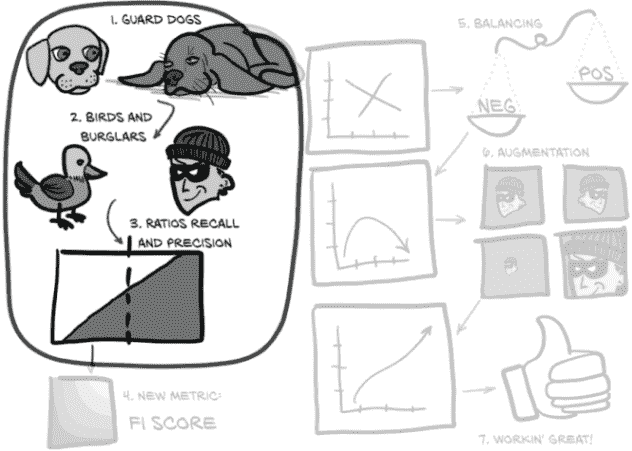

我们不再考虑模型和肿瘤,而是考虑图 12.3 中的两只看门狗,它们刚从服从学校毕业。它们都想警告我们有窃贼——这是一种罕见但严重的情况,需要及时处理。

图 12.3 本章的主题集,重点放在框架比喻上

不幸的是,虽然两只狗都是好狗,但都不是好的警卫狗。我们的梗犬(Roxie)对几乎所有事情都会吠,而我们的老猎犬(Preston)几乎只会对入室者吠叫——但前提是他在他们到达时恰好醒着。

Roxie 几乎每次都会警告我们有入室者。她还会警告我们有消防车、雷暴、直升机、鸟、邮递员、松鼠、路人等。如果我们对每次吠叫进行跟进,我们几乎永远不会被抢劫(只有最狡猾的偷窃者才能溜过)。完美!… 除了那么勤奋意味着我们实际上并没有通过养警卫狗节省任何工作。相反,我们每隔几个小时就会起床,手持手电筒,因为 Roxie 闻到了猫的气味,或者听到了猫头鹰的叫声,或者看到了一辆晚点的公共汽车经过。Roxie 有一个问题性的假阳性数量。

假阳性是被分类为感兴趣或所需类别的成员(阳性表示“是的,这是我感兴趣了解的类型”)的事件,但实际上并不是真正感兴趣的。对于结节检测问题,当一个实际上无趣的候选者被标记为结节,因此需要放射科医生的关注时,就会发生假阳性。对于 Roxie 来说,这些可能是消防车、雷暴等。在接下来的章节和随后的图中,我们将使用一张猫的图片作为典型的假阳性。

将假阳性与真阳性进行对比:被正确分类的感兴趣项目。这些将在图中由一个人类强盗表示。

与此同时,如果 Preston 吠叫,请立即报警,因为这意味着几乎肯定有人闯入,房子着火了,或者哥斯拉在袭击。然而,Preston 睡得很沉,正在进行家庭入侵的声音不太可能唤醒他,所以每当有人尝试时,我们几乎总是会被抢劫。虽然比没有好,但我们并没有真正获得最初让我们养狗的平静心态。Preston 有一个问题性的假阴性数量。

假阴性是被分类为不感兴趣或不是所需类别的成员(阴性表示“不,这不是我感兴趣了解的类型”)的事件,但实际上确实是感兴趣的。对于结节检测问题,当一个结节(即潜在的癌症)未被检测到时,就会发生假阴性。对于 Preston 来说,这些将是他睡过的抢劫案。在这里我们将有点创意,使用一张啮齿强盗的图片来代表假阴性。它们很狡猾!

将假阴性与真阴性进行对比:正确识别为无趣项目的项目。我们将用一只鸟的图片来代表这些。

为了完成这个比喻,第十一章的模型基本上是一只拒绝对不是金鱼罐的任何东西发出喵声的猫(同时坚定地忽视 Roxie)。我们在上一章末尾的重点是整体训练和验证集的正确百分比。显然,这不是一个很好的评分方式,正如我们从我们每只狗对单一指标的近视关注——比如真阳性或真阴性的数量——可以看出的那样,我们需要一个更广泛关注的指标来捕捉我们的整体表现。